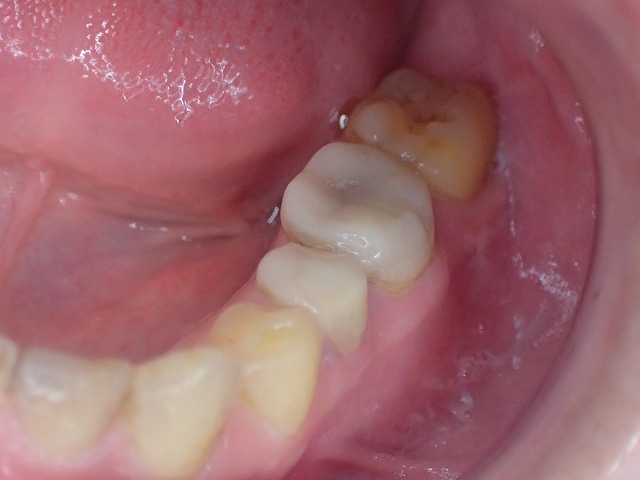

左下

プラスチック冠 おそらくcad/cam冠

かもしれません。

歯と歯はお互いに接触しなくてはなりません。

「コンタクト」と言って歯科では重要視される

状態で、適切なコンタクトが歯周病や虫歯、

咬み合わせなどに関与しています。

右下

同じくコンタクトしていません。

cad/cam冠はすぐに減るので

お口の中を大切に思いう人は、入れないほうが

良いと思います。

左側のcad/cam冠をジルコニアクラウンに交換

激しい歯ぎしりでCAD/CAM冠が

大きく摩耗しています。

そのため歯と歯の間に隙間ができています。

ジルコニアクラウンに交換

左側のCAD/CAM冠を除去してジルコニアを制作

cad/cam冠などのプラスチック関係の

かぶせ物は、歯肉に炎症を起こす場合がほとんどです。

両側の摩耗したCAD/CAM冠を

ジルコニアクラウンに交換できました。